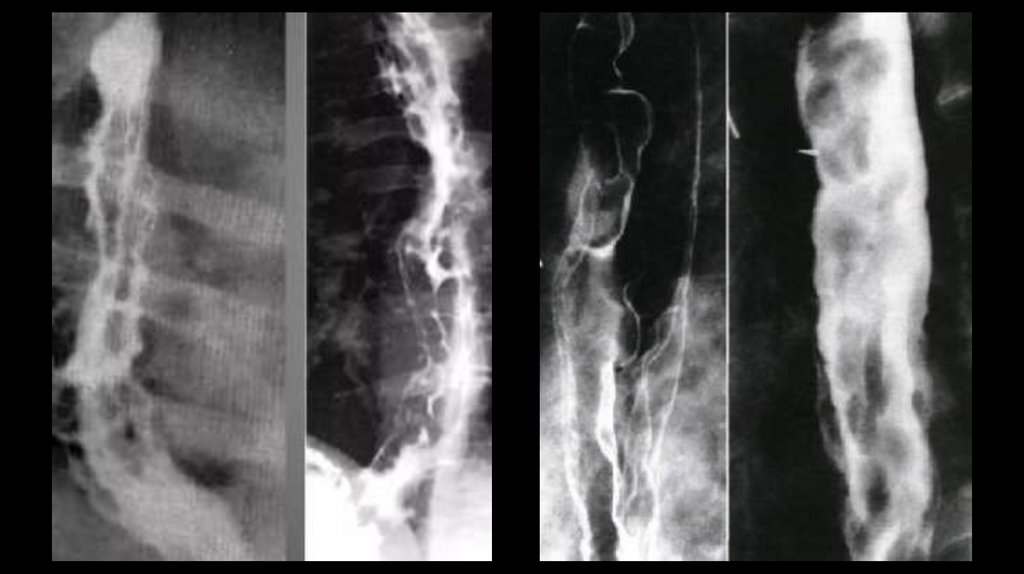

• «Пищевод щелкунчика» (синоним — сегментарный спазм пищевода) —

нарушение моторики пищевода, при котором наблюдаются сокращения

дистальной части пищевода высокой амплитуды и большой длительности.

Некоторые симптомы: дисфагия, сильная боль в груди. Заболевание может

протекать бессимптомно.

• «Пищевод щелкунчика» — доброкачественное, непрогрессирующее

заболевание, не приводящее к серьёзным осложнениям.